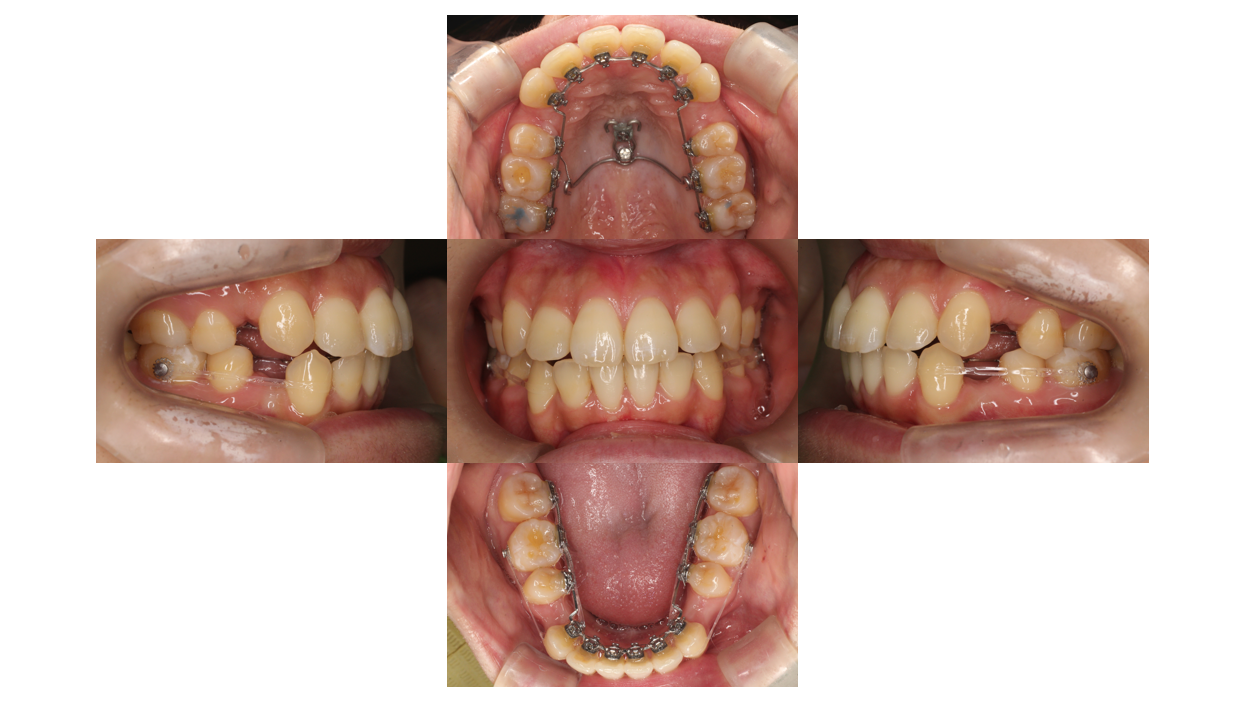

装置装着後

叢生・出っ歯症例

装着を装着しました。

奥歯にバイトアップを装着することで、装置が外れにくくしています。